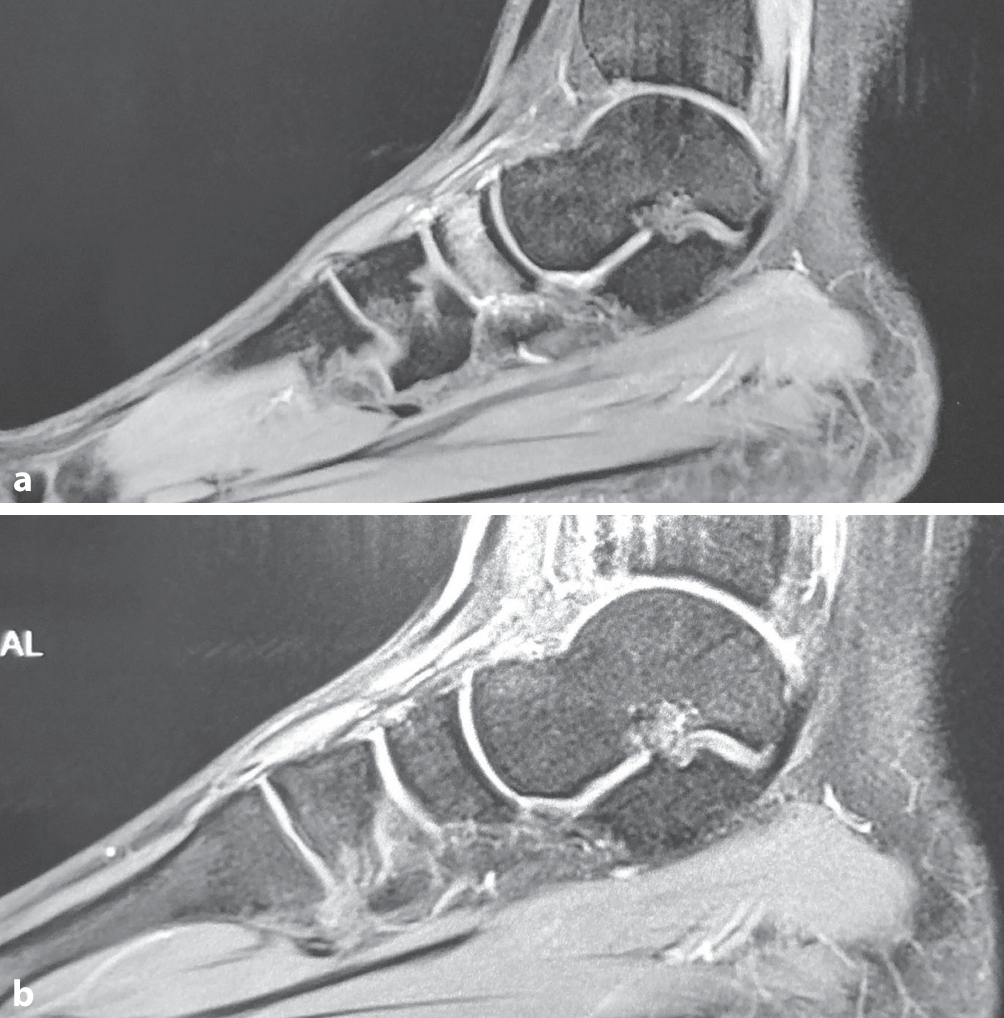

Um die Rückkehr zum Sport noch weiter zu beschleunigen, gibt es einige Hinweise, die eine Kombinationstherapie mit der Stoßwellentherapie vorschlagen, beispielsweise für die Kombination ESWT und „platelet rich plasma“ (PRP) [27] oder die Kombination von ESWT und oszillierender Magnetfeldtherapie (EMTT; Abb. 5 und 6; [28, 29]).

Abb. 5

Stressfraktur des Os cuboideum mediale vor (a) und 6 Wochen nach (b) 3 Sitzungen kombinierter extrakorporaler Stoßwellentherapie (ESWT) und extrakorporaler Magnetotransduktionstherapie (EMTT) bei einer 15 Jahre jungen Hürdensprinterin

Abb. 6

Fokussierte elektromagnetische Stosswellentherapie (ESWT; Abb. 6a) und b extrakorporale Magnetotransduktionstherapie (EMTT) bei medialer Sesambeinfraktur